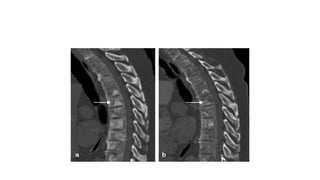

99Tc BONE SCAN

• Clinically apparent metastatic disease limited to bone in 80-85% of patients of

metastatic ca prostate

• A close correlation exists between pretreatment PSA level and incidence of

abnormal bone scan results

• Osteoblastic secondaries

• MC sites of metastasis

• Vertebral column- 74%

• Ribs- 70%

• Pelvis- 60%

• Femora- 44%

• Shoulder girdle-41%

• Indications: Pretherapy

• Post therapy: Skeletal symptoms in associate with ↑PSA level

• False +ve

• Fractures/ Arthritis / Paget’s disease